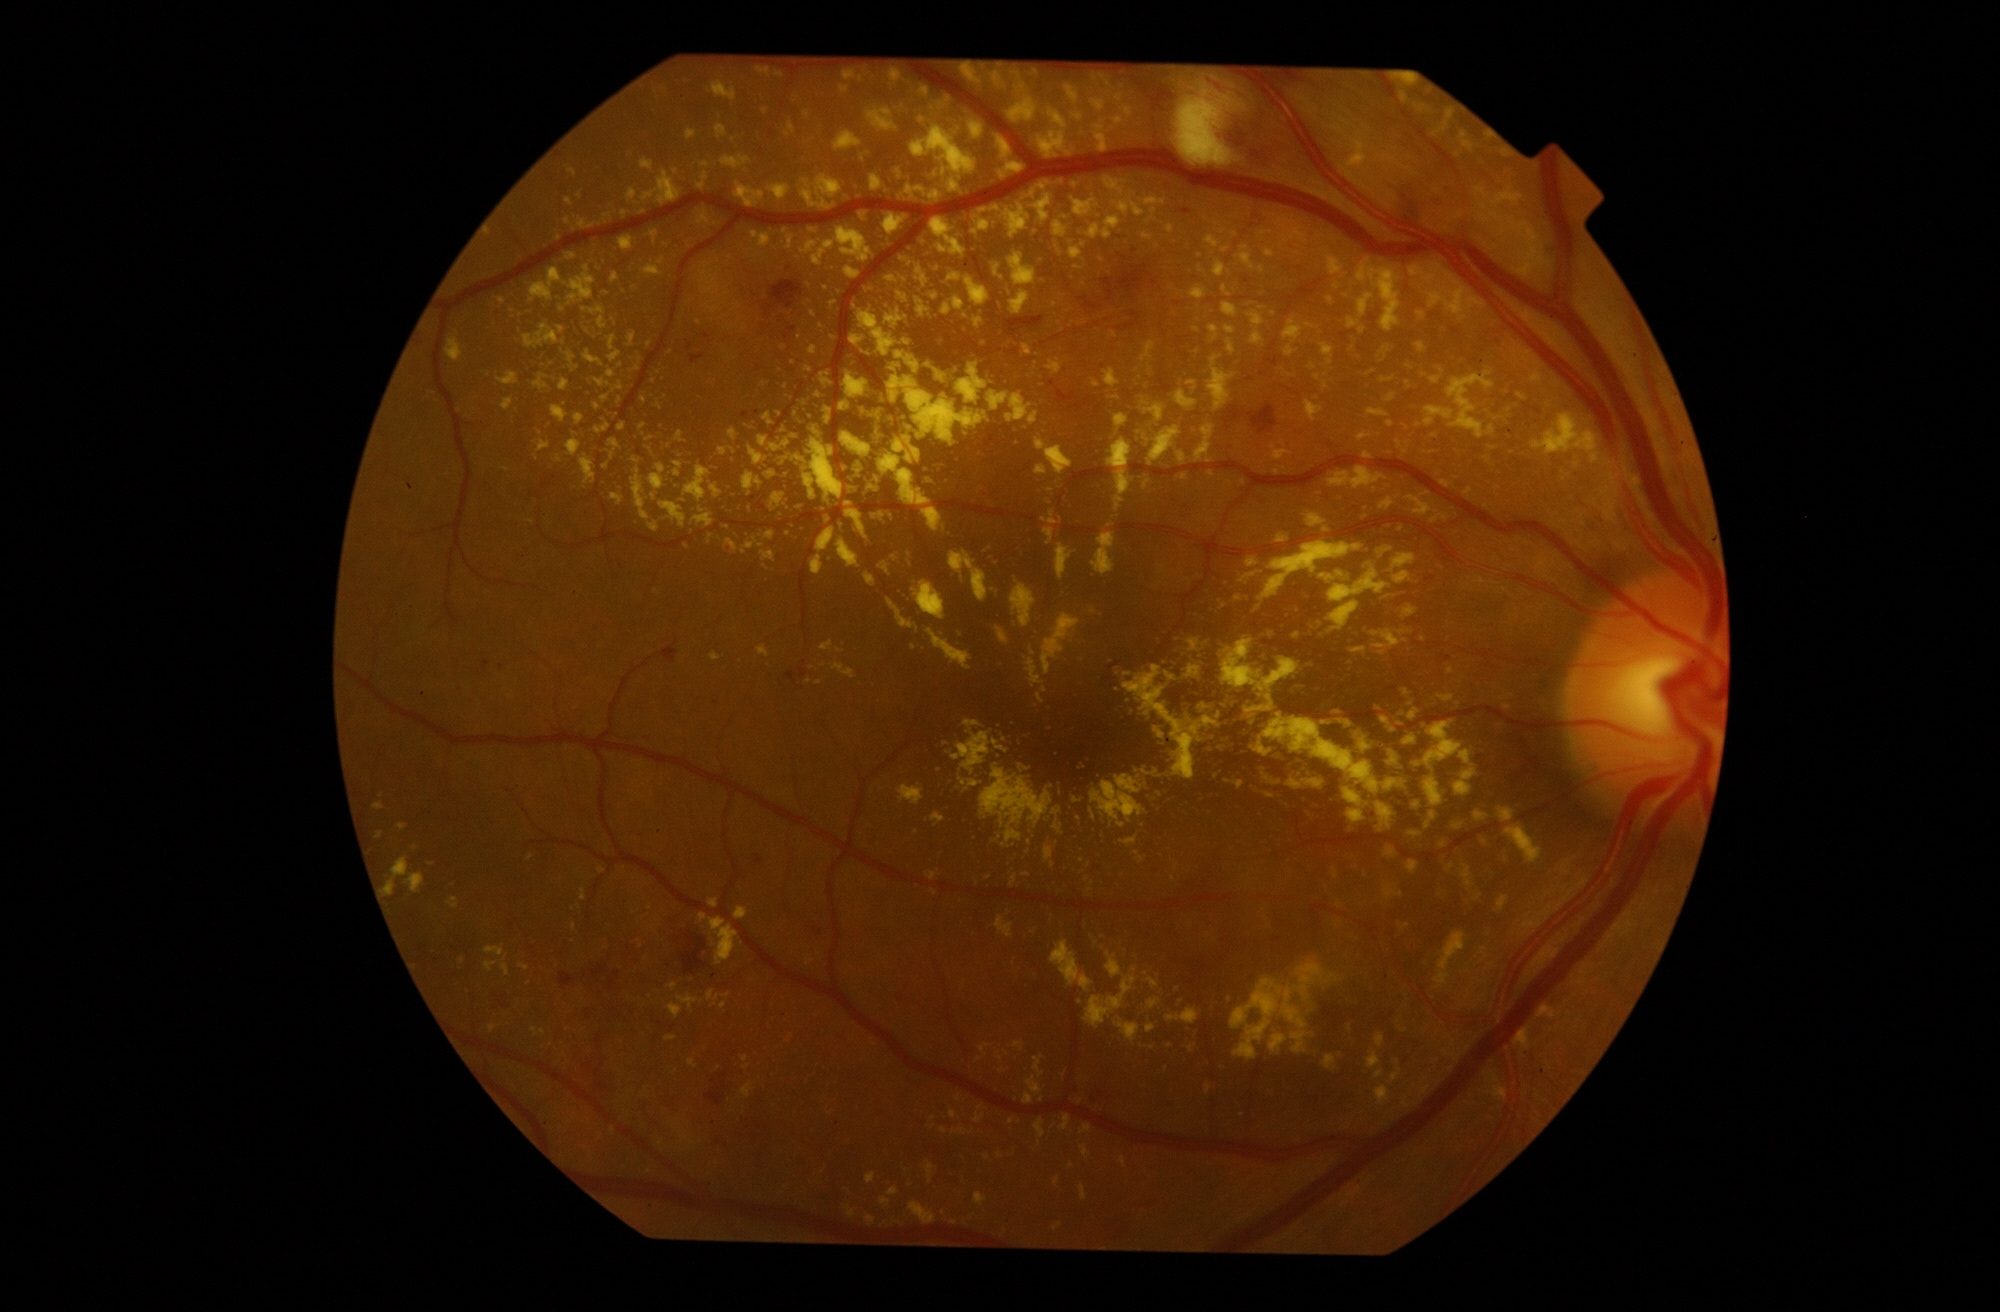

El edema macular diabético es la causa más frecuente de pérdida de visión en la población diabética.

→ Leer más